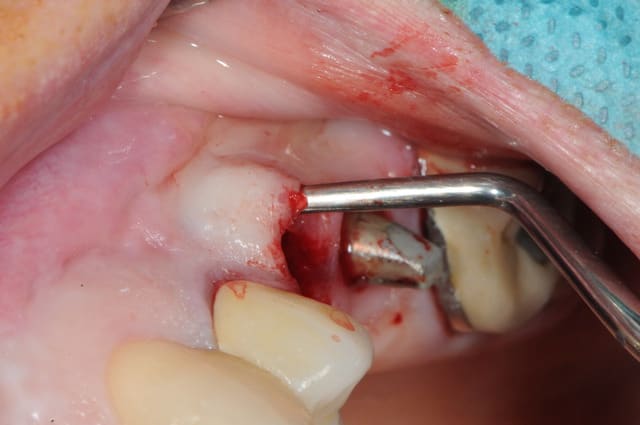

17/09/2011 à 20h19

merci céramique!

c'est peut être un hasard, mais le patient est justement passé aujourd'hui. j'en ai bien sure profité pour faire une photo...

on est ici à j+5 mois, pas de perte osseuse vestibulaire.

la pose d'implant ( flapless très certainement) est prévue pour dans 15 jours.